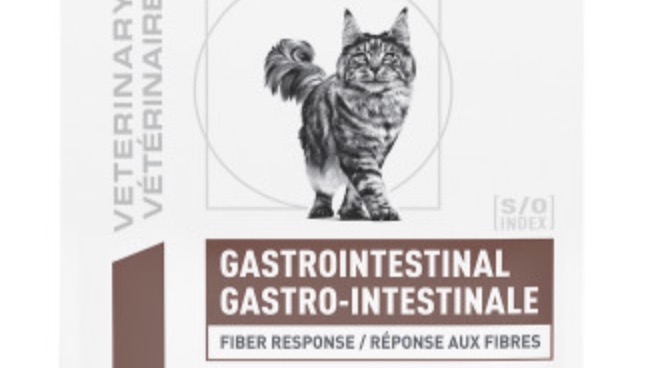

She has had constipation in the past but for a little over a year now I've had no issues due to a special gastro-intestinal prescription diet that worked. A couple weeks ago I picked up a new bag of food from my vet (can't go in due to Covid) and within a week Luna developed constipation. I called Royal Canin to ask if the formula had recently changed; they asked me to describe the bag, and immediately told me I received the wrong food and that "this happens all the time." There apparently are two identical gastrointestinal bags, but our vet clinic had handed me the wrong one that didn't have "fiber response" listed in a small white box below the name.

See the zoomed in photos of the two bags...if anything comes from this, I hope it's that the company changes the appearance of these two bags, especially if "this happens all the time." This was a medication error which negatively impacted my poor kitty and has left me with >10k of debt.